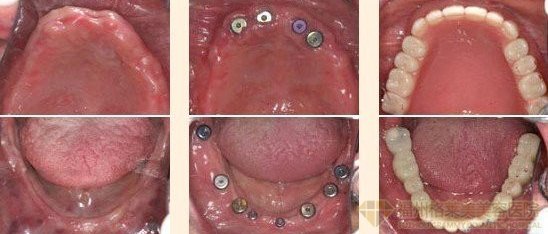

种植牙齿有危害吗?据牙科介绍种植牙是目前连锁上流行的牙齿修复方法之一,种植牙是很的对人没有危害。但是并不排除其它可能,比如医院条件不达标,经验、差等,就会给人带来极大的危害。

所以,做种植牙一定要选择正规专业的医院。一是有着品质保障,二是减少手术可能带来的危害。那么广州种植牙哪家好呢?